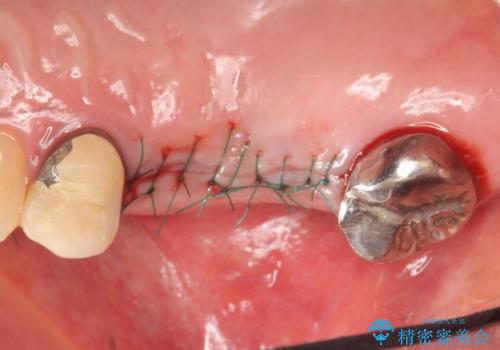

右上の567ブリッジを外したところ、右上5は歯根破折により保存不可能だったため、右上56部にインプラントを埋入し欠損補綴を行いました。

今回用いたオールセラミッククラウンはジルコニアフレームという白い素材の上にセラミックを盛っているため、審美性が非常に高いのが特徴です。

また、ジルコニアは人工ダイヤモンドの材料にも使われているほど高い強度を持っており、そのためオールセラミッククラウンは審美性だけでなく、奥歯やブリッジの補綴も可能とするクラウンです。

カスタムアバットメントは患者様それぞれの歯茎に合わせて製作されたオーダーメイドのアバットメントです。

既製のアバットメントに比べ適合がよく、高い清掃性を誇ります。